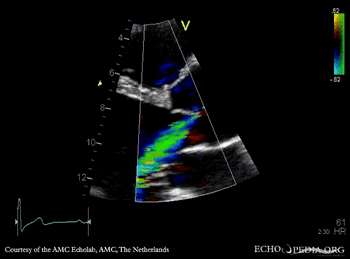

E00551.gif

PLAX: dilated aortic root PLAX: 2-D measurement of aortic root

E00554.gif

M-Mode through aortic root PLAX with Color Doppler: moderate aortic regurgitation